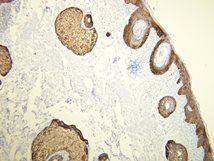

Anti-Cytokeratin 14

Rabbit clonal antibody

Product ID:DB 099 Category:IHC-P

IHC-P, dilution 1:100

Gallery